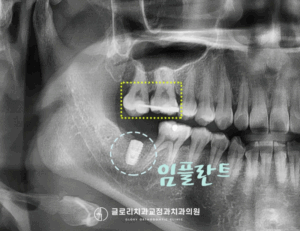

망우동 치과 정중선 편위 및 삐뚤어진 치열, 가지런한 배열을 회복하기 위한 발치 교정

안녕하세요 망우동 치과 김정은 원장입니다. 치아가 삐뚤어 교정 상담을 받게 되면 많은 분들이먼저 궁금해하시는 것이 바로 비발치 인지 발치 교정인지에 대한 부분입니다. 23.07.18 가능하다면 치아를 뽑지않고 배열만 정리하는 비발치 방식을…